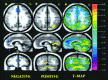

The level of familiarity of a given stimulus plays an important role in memory processing. Indeed, the novelty/familiarity of learned material has been proven to affect the pattern of activations during recognition memory tasks. We used visually presented words to investigate the neural basis of recognition memory for relatively novel and familiar stimuli in schizophrenia. Subjects were 34 healthy volunteers and 19 schizophrenia spectrum patients. Two experimental cognitive conditions were used: 1 week and again 1 day prior to the PET imaging subjects had to thoroughly learn a list of 18 words (well-learned memory). Subjects were also asked to learn another set of 18 words presented 1 min before the PET experiment (novel memory). During the PET session, subjects had to recognize the list of 18 words among 22 new (distractor) words. Subjects also performed a control task (reading words). A nonparametric randomization test and a statistical t-mapping method were used to determine between- and within-group differences. In patients the recognition of novel material produced relatively less flow in several frontal areas, superior temporal gyrus, insular cortex, and parahippocampal areas, and relatively higher activity in parietal areas, visual cortex, and cerebellum, compared to controls. No significant differences in flow were seen when comparing well-learned memory activations between groups. These results suggest that different neural pathways are engaged during novel recognition memory in patients with schizophrenia compared to healthy individuals. During recognition of novel material, patients failed to activate frontal/limbic regions, recruiting a set of posterior perceptual brain regions instead.